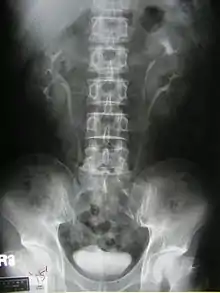

Diagnosis

Prenatally diagnosed hydronephrosis (fluid-filled kidneys) suggest post-natal follow-up examination. The strongest neo-natal presentation is urinary tract infection. A hydronephrotic kidney may present as a palpable abdominal mass in the newborn, and may suggest an ectopic ureter or ureterocele. In older children, ureteral duplication may present as: